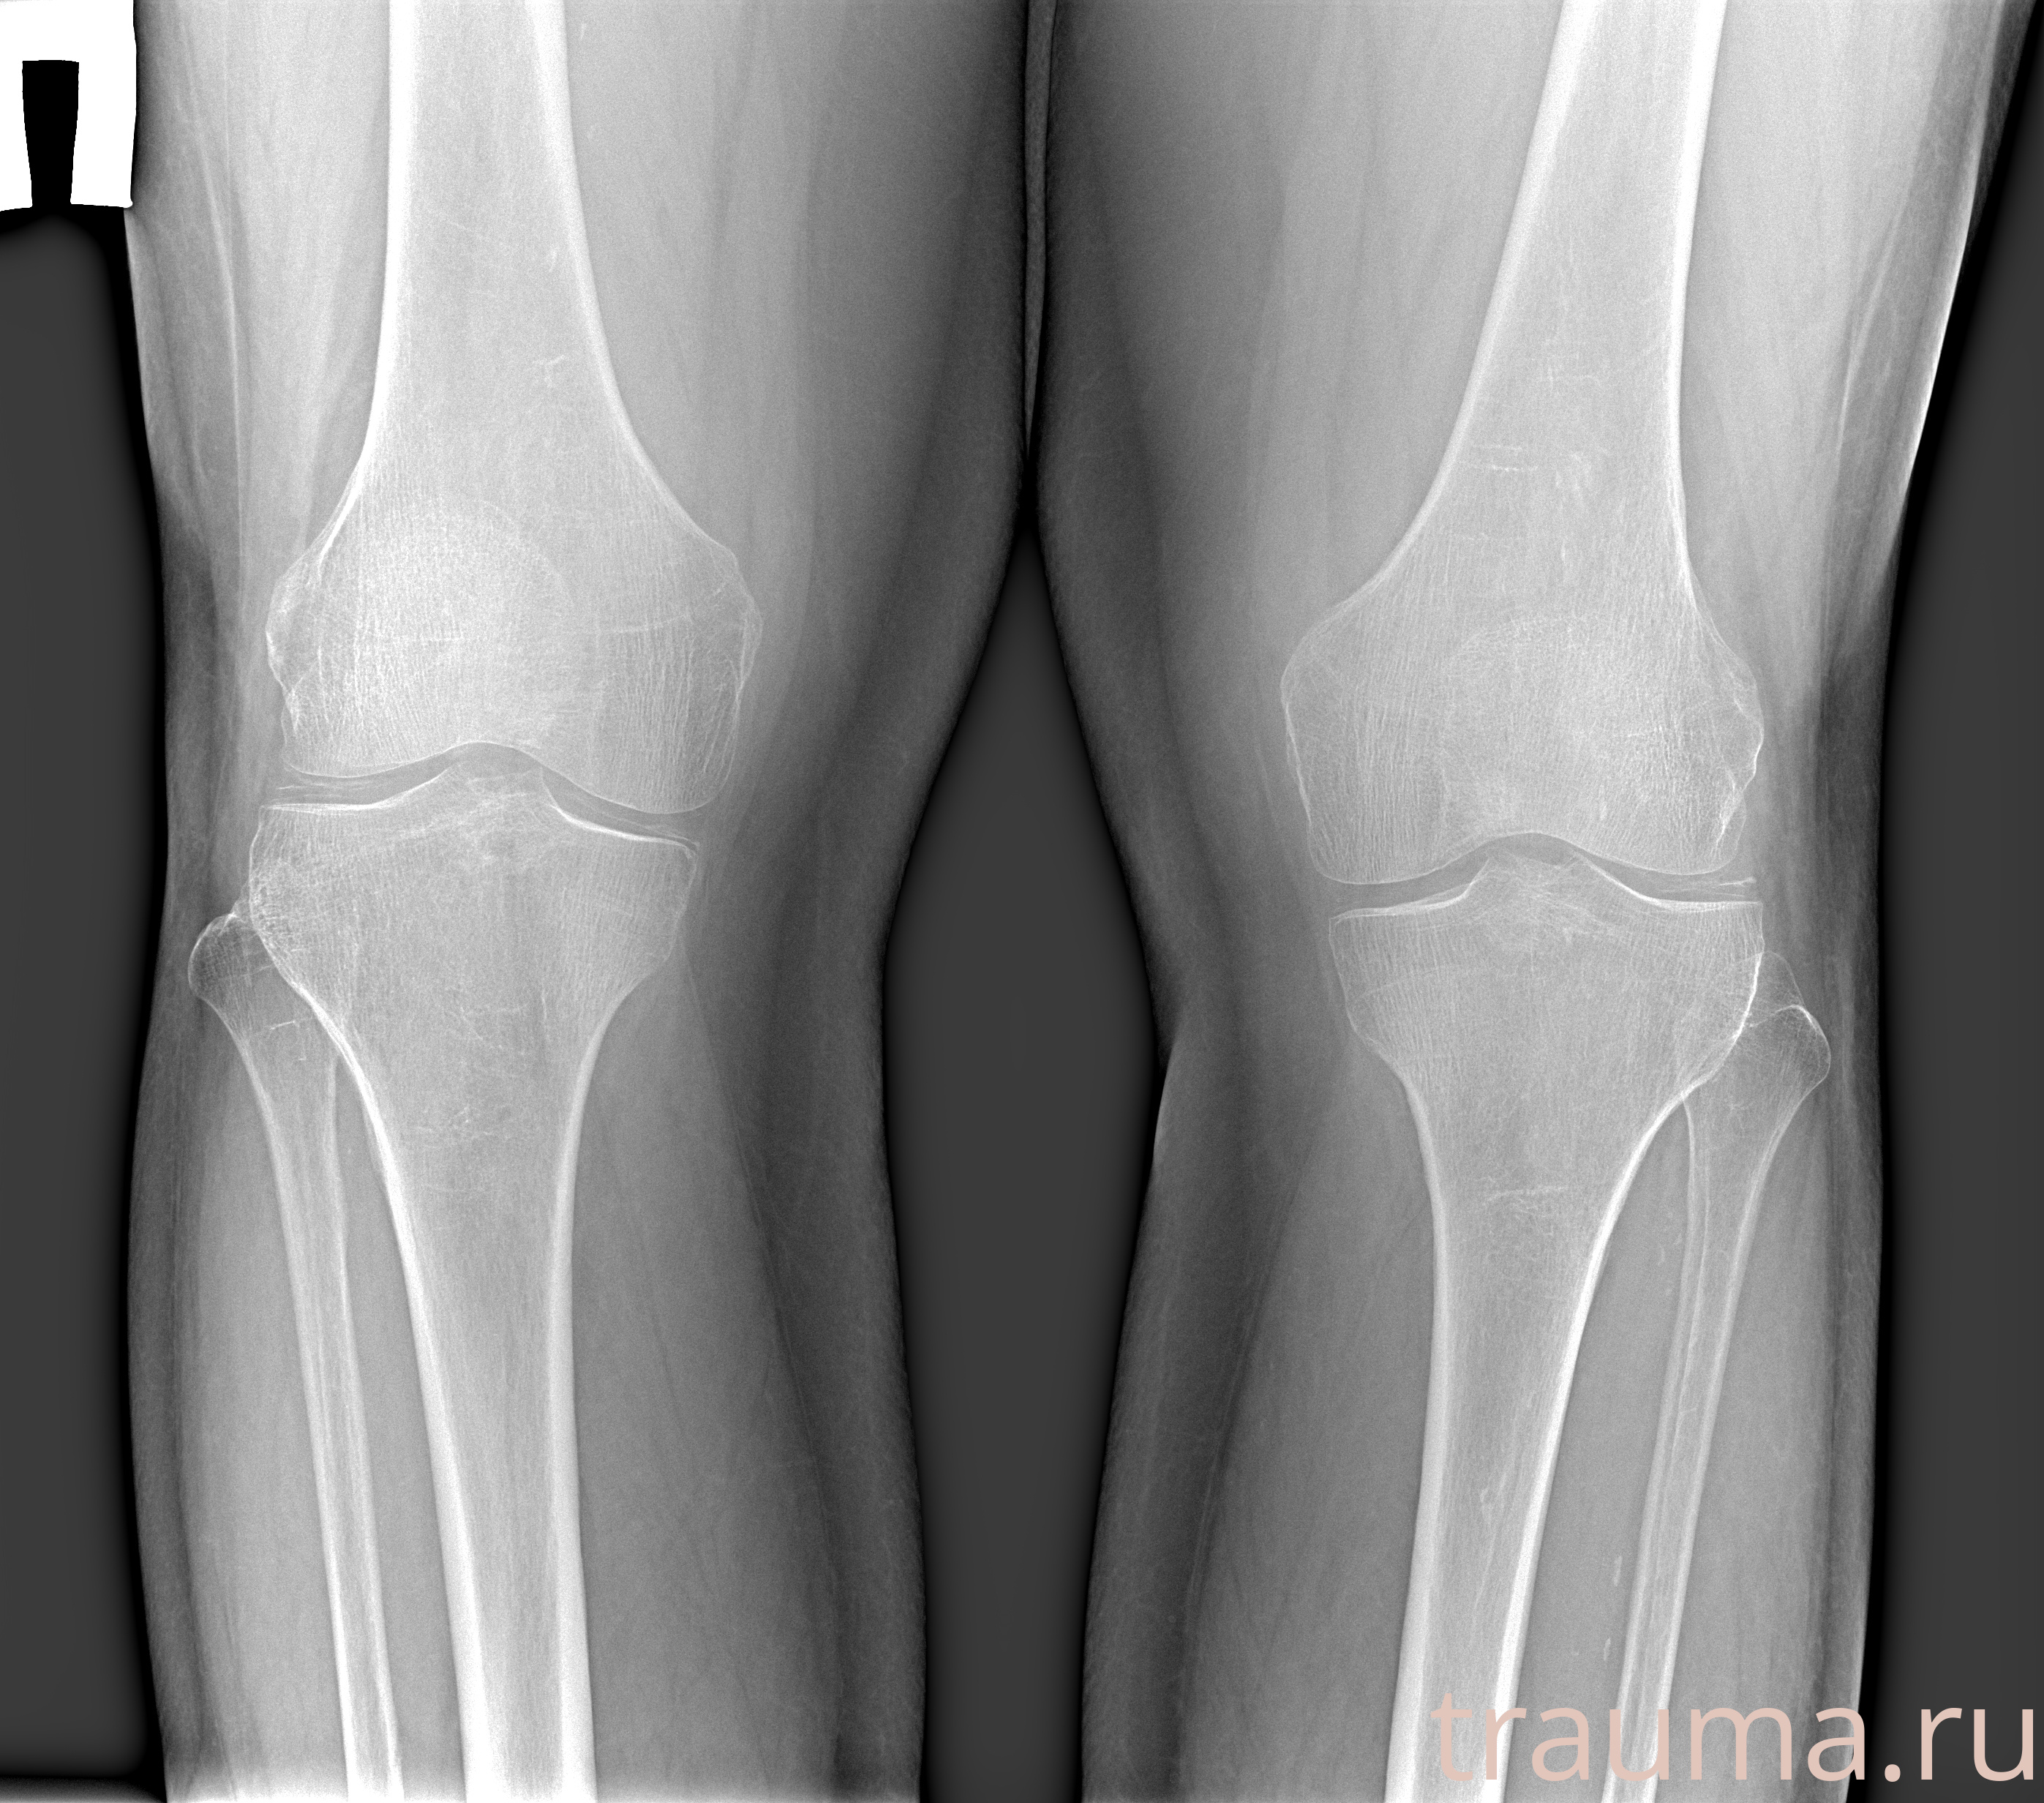

Рентгенограммы

Рентген на дому: по вашему адресу приезжает врач-рентгенолог, травматолог-ортопед с мобильным рентгеновским аппаратом, проводит диагностику травмы или заболевания, делает необходимые рентгенограммы, дает рекомендации по дальнейшему лечению. Получить качественные снимки в домашних условиях возможно благодаря уникальной методике, разработанной МосРентген Центром для института  Склифосовского